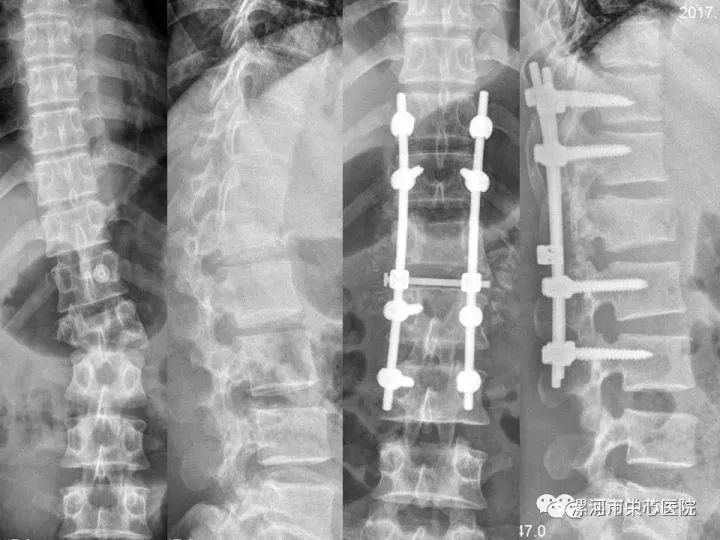

晚上10点,最后一台脊柱骨折并瘫痪的患者手术接近尾声。该患者是腰1椎体三柱骨折,患者的脊柱极度稳定,脊柱侧方移位、成角并后凸畸形,腰1椎体前缘的高度压缩的只剩下不足1/10,李程协助关节脊柱外科副主任兼脊柱外科副主任李玉伟,经过细心、仔细的矫形,不但对脊髓完全减压,而且椎体的高度接近完全恢复、侧后凸畸形完全纠正。

图:术前脊柱三柱骨折、侧后凸畸形,腰1椎体前缘压缩到不足1/10。术后椎体高度接近完全恢复、侧后凸畸形完全纠正